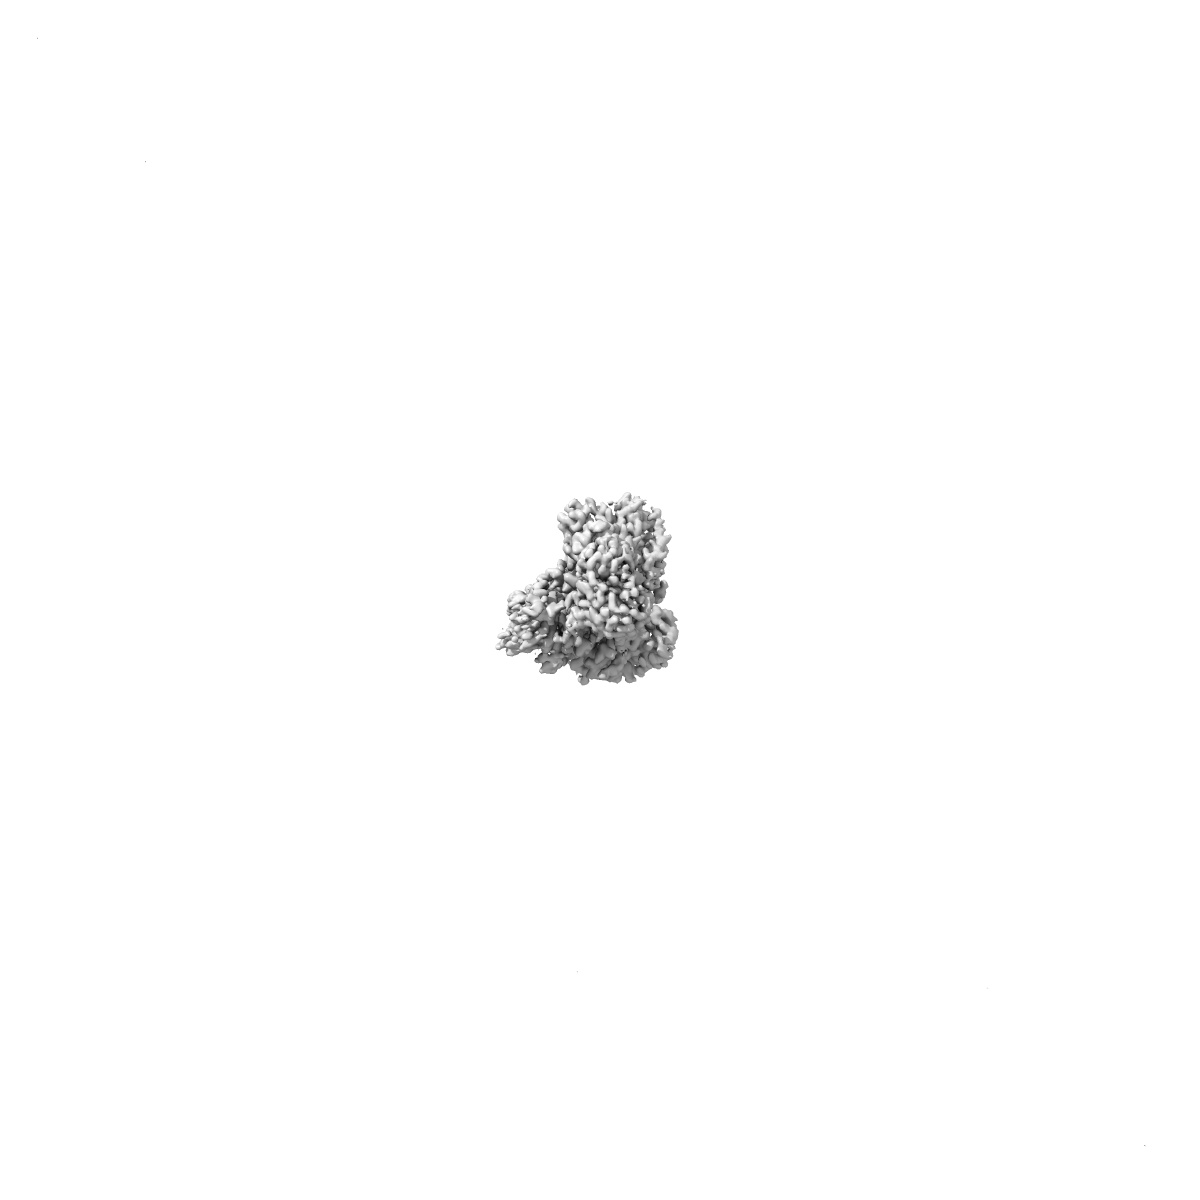

Cryo-EM structure of CDK2/CyclinE1 in complex with CRBN/DDB1 and Cpd 4 (local mask)

Single-particle

2.84 Å

Sample: Cryo-EM structure of CDK2/CyclinE1 in complex with CRBN and Cpd 4

Fitted models: 9d0x

CDK2 heterobifunctional degraders co-degrade CDK2 and cyclin E resulting in efficacy in CCNE1-amplified and overexpressed cancers.